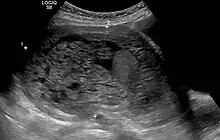

Transvaginal ultrasonography showing a molar pregnancy

Molar pregnancy in ultrasound

The diagnosis is strongly suggested by ultrasound (sonogram), but definitive diagnosis requires histopathological examination. On ultrasound, the mole resembles a bunch of grapes ("cluster of grapes" or "honeycombed uterus" or "snow-storm").[14] There is increased trophoblast proliferation and enlarging of the chorionic villi, and angiogenesis in the trophoblasts is impaired.[15]